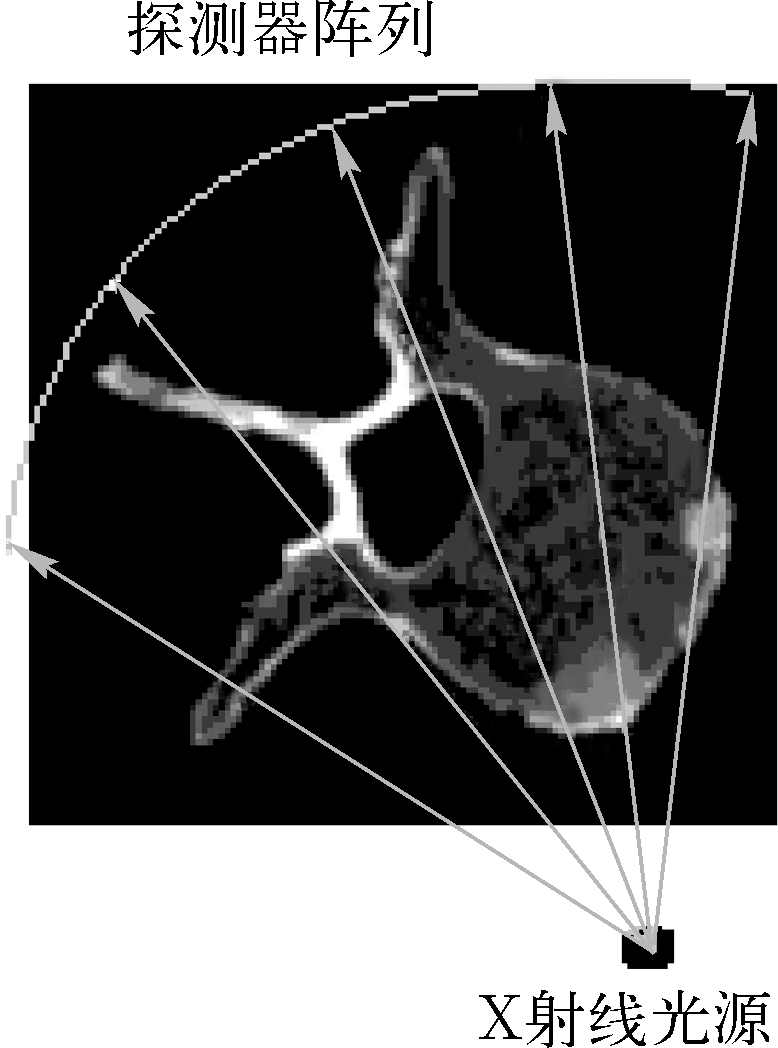

CT解决了X线成像的影像重叠问题,能够获得人体断层图像。CT也需要X射线。X射线管发出X射线经准直器准直后成为一窄束X射线,该X射线对人体的某一特定层面从各个角度进行投射,如图1.8所示。透过人体的X射线由探测器接收后,送到计算机进行数据处理,从投影数据(即探测器接收到的强度值)推算出图像像素对应的密度值 [4] ,从而实现对人体的断层成像。通过逐层对人体某一部位器官扫描获得一系列断层图像,对这些断层图像进行三维重建和可视化,即可获得该器官结构的三维图像。

图1.8 CT